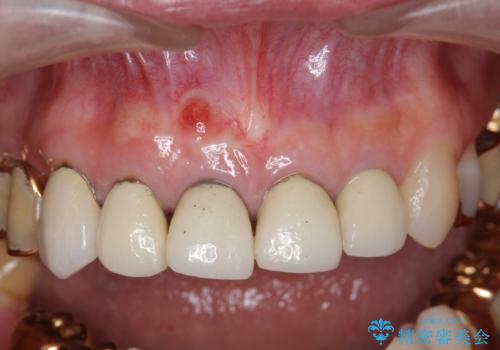

- 前歯の痛み・排膿・ぐらつきの改善を求めて来院されました。

視診・X線写真検査より根尖性歯周炎が認められ再治療が必要な状態です。